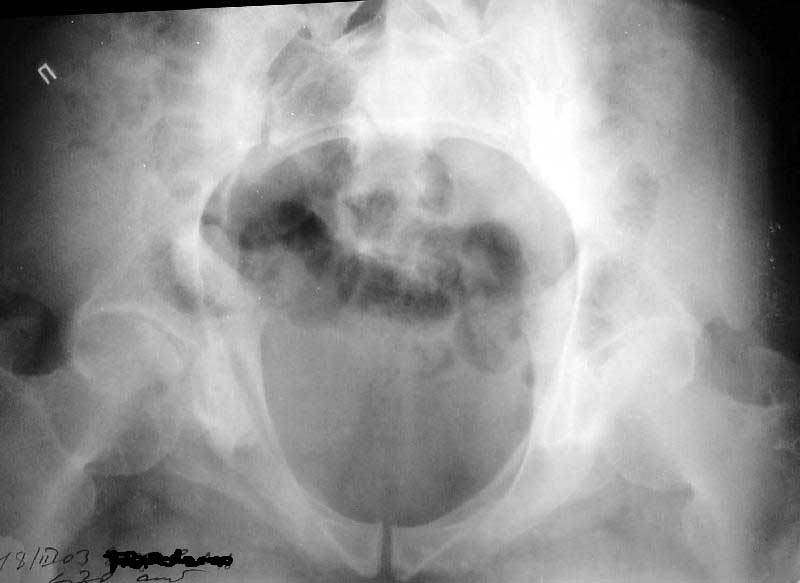

ФасInlet

Как то не очень укладываются тянущие боли в нижних конечностях с посттравматическим правосторонним т.е односторонним сакроилеитом.

Как Вы сами видели на томограммах, грубых деструктивных явлений крестцово-подвздошного сочленения не определяется( маркировка правая -левая сторона не видна), определяется сравнительно незначительное расширение суставной щели с одной стороны и не более того.

Виноват, первый раз не обратил внимания на возможность полноформатного просмотра томограмм. В этой связи -дополнения к своему первому комментарию: сросшийся перелом вертлужной впадины справа, L5-S1 спондилоартроз, расширение суставной щели крестцово-подвдзошного сочленения справа может компрометировать его стабильность и вызывать локальные боли, но вряд ли это может давать двусторонние проявления в нижних конечностях. Все-таки миелограмма или ЯМР желательно иметь, чтобы определиться в тактике.

Речь идёт о коплексном двустороннем повреждении таза с нарушением тазового кольца.

А именно: разрыв илио-сакрального сочленения справа, на этой же стороне трансацетабулярный перелом с незначительным смещением, перелом подвздошной кости слева. Исходя из вышеперечисленного, меня не удивляют двусторонние жалобы пациента. Однако, учитывая представленные снимки ЯМР и времени, прошедшим с момента травмы мне представляется пока преждевременным говорить об образовании ложных суставов. Судя по развиввшейся костной мозоли в области вышеперечисленных очагов, все переломы находяться в стадии консолидации. Вполне возможно, однако, что трансацетабулярный перелом приведёт в дальнейшем к развитию посттравматического артроза ТБ- сустава.